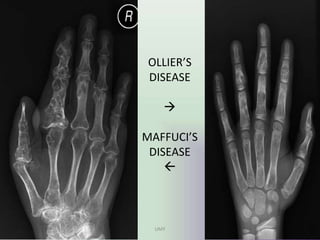

OLLIER”S DISEASE

• Ollier disease also known as

enchondromatosis, is a non-

hereditary, sporadic, skeletal

disorder characterised by

multiple enchondromas that are

principally located in the

metaphyseal regions.

• Plain films show multiple

enchondromas. Larger lesions can

show cartilage calcification in a

typical rings and arcs pattern.

• Imaging characterestics are of

same as ENCHONDROMAS

MAFUCCI’S SYNDROME

• Maffucci syndrome is a congenital non

hereditary mesodermal dysplasia characterised

by multiple enchondromas with soft-tissue

cavernous haemangiomas.

• Imaging findings are

multiple enchondromas seen associated with

soft tissue swelling and phleboliths.

• Enchondromas degenerate into

chondrosarcomas in 15-51% of cases and soft-

tissue haemangiomas to vascular sarcomas in

3-5%.

UMY

OLLIER’S

DISEASE



MAFFUCI’S

